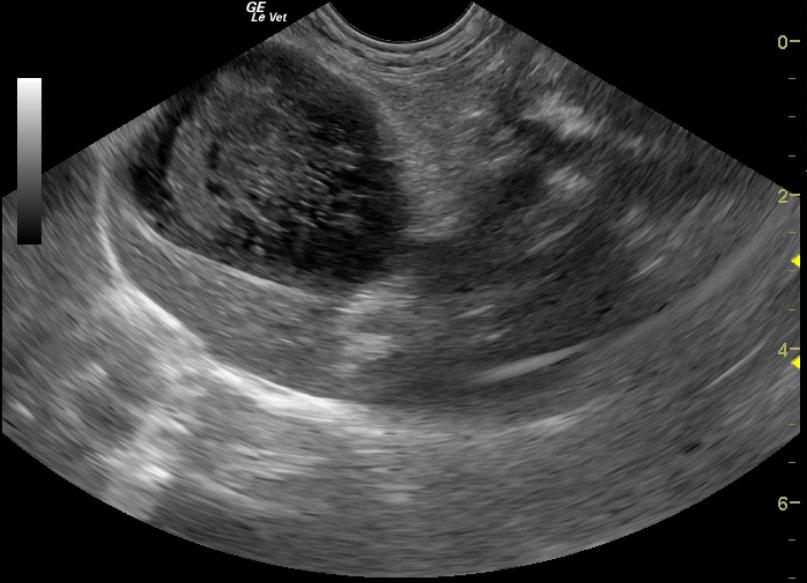

A 12-year-old FS Pomeranian was presented for acute vomiting and diarrhea. On physical examination, dyspnea, coughing, and a heart murmur were present. Urinalysis, T4, coagulation profile, and CBC were all within normal limits. Abnormalities on serum biochemistry were revealed elevated total proteins, globulin, liver enzyme activity, total bilirubin, and azotemia.